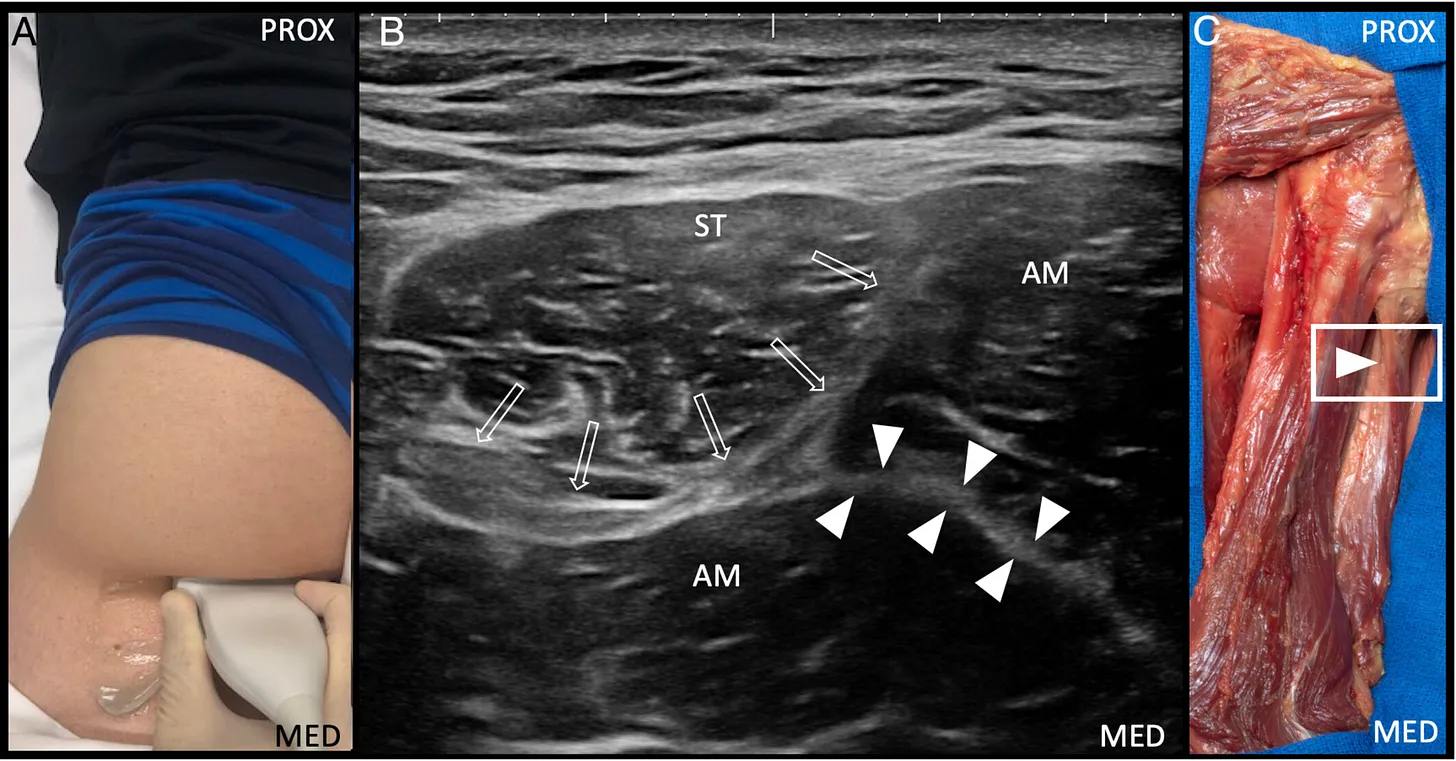

A. Posición anatómica axial del transductor ecográfico, situada medial al “triángulo hiperecogénico”, para la visualización del tendón de origen isquiocondíleo del aductor mayor.

B. Imagen ecográfica en corte transversal del tendón de origen isquiocondíleo del aductor mayor (puntas de flecha blancas).

C. Preparación cadavérica que muestra la posición del transductor para la visualización del tendón de origen isquiocondíleo del aductor mayor.

AM: músculo aductor mayor;

BF: músculo bíceps femoral (cabeza larga);

ST: músculo semitendinoso;

GM: músculo glúteo mayor;

MED: medial; PROX: proximal;

rectángulo blanco: posición del transductor;

flechas abiertas: tendón del semimembranoso.